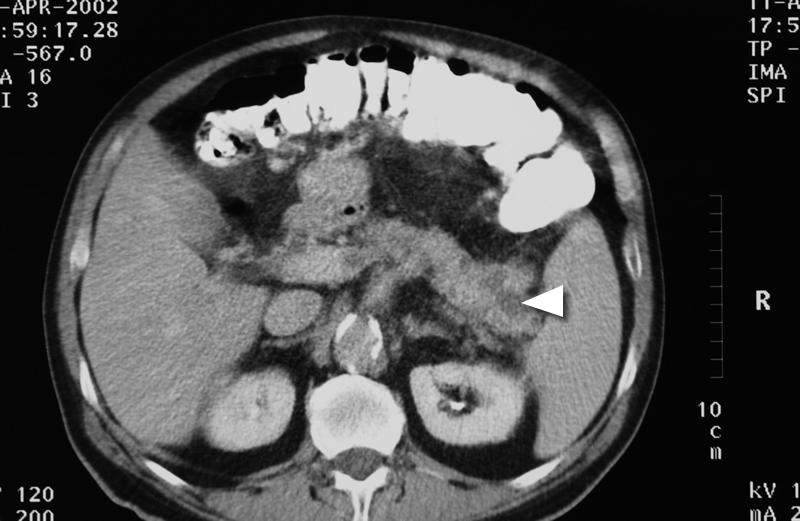

For tumours that involve the body and the tail of the pancreas, a left sided or distal pancreatectomy is performed. This involves removal of the body and tail of pancreas together with spleen and surrounding lymph node tissue. In selected patients this procedure is amenable to a laparoscopic or keyhole approach.

CT scan showing tumour in the tail of the pancreas.